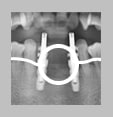

08.02.15 인공뼈

이식술 후, 사진

: 잇몸뼈가 재생된 후,

임플란트 재식립을

하였고, 보철 제작

시행 전, 임플란트와

잇몸뼈 사이의 결합도를

확인하였다.

13.07.31 보철제작 후, 약 5년 경과 사진

: 약간의 잇몸뼈 흡수가 관찰되지만,

훌륭한 stability를 유지하고 있다.